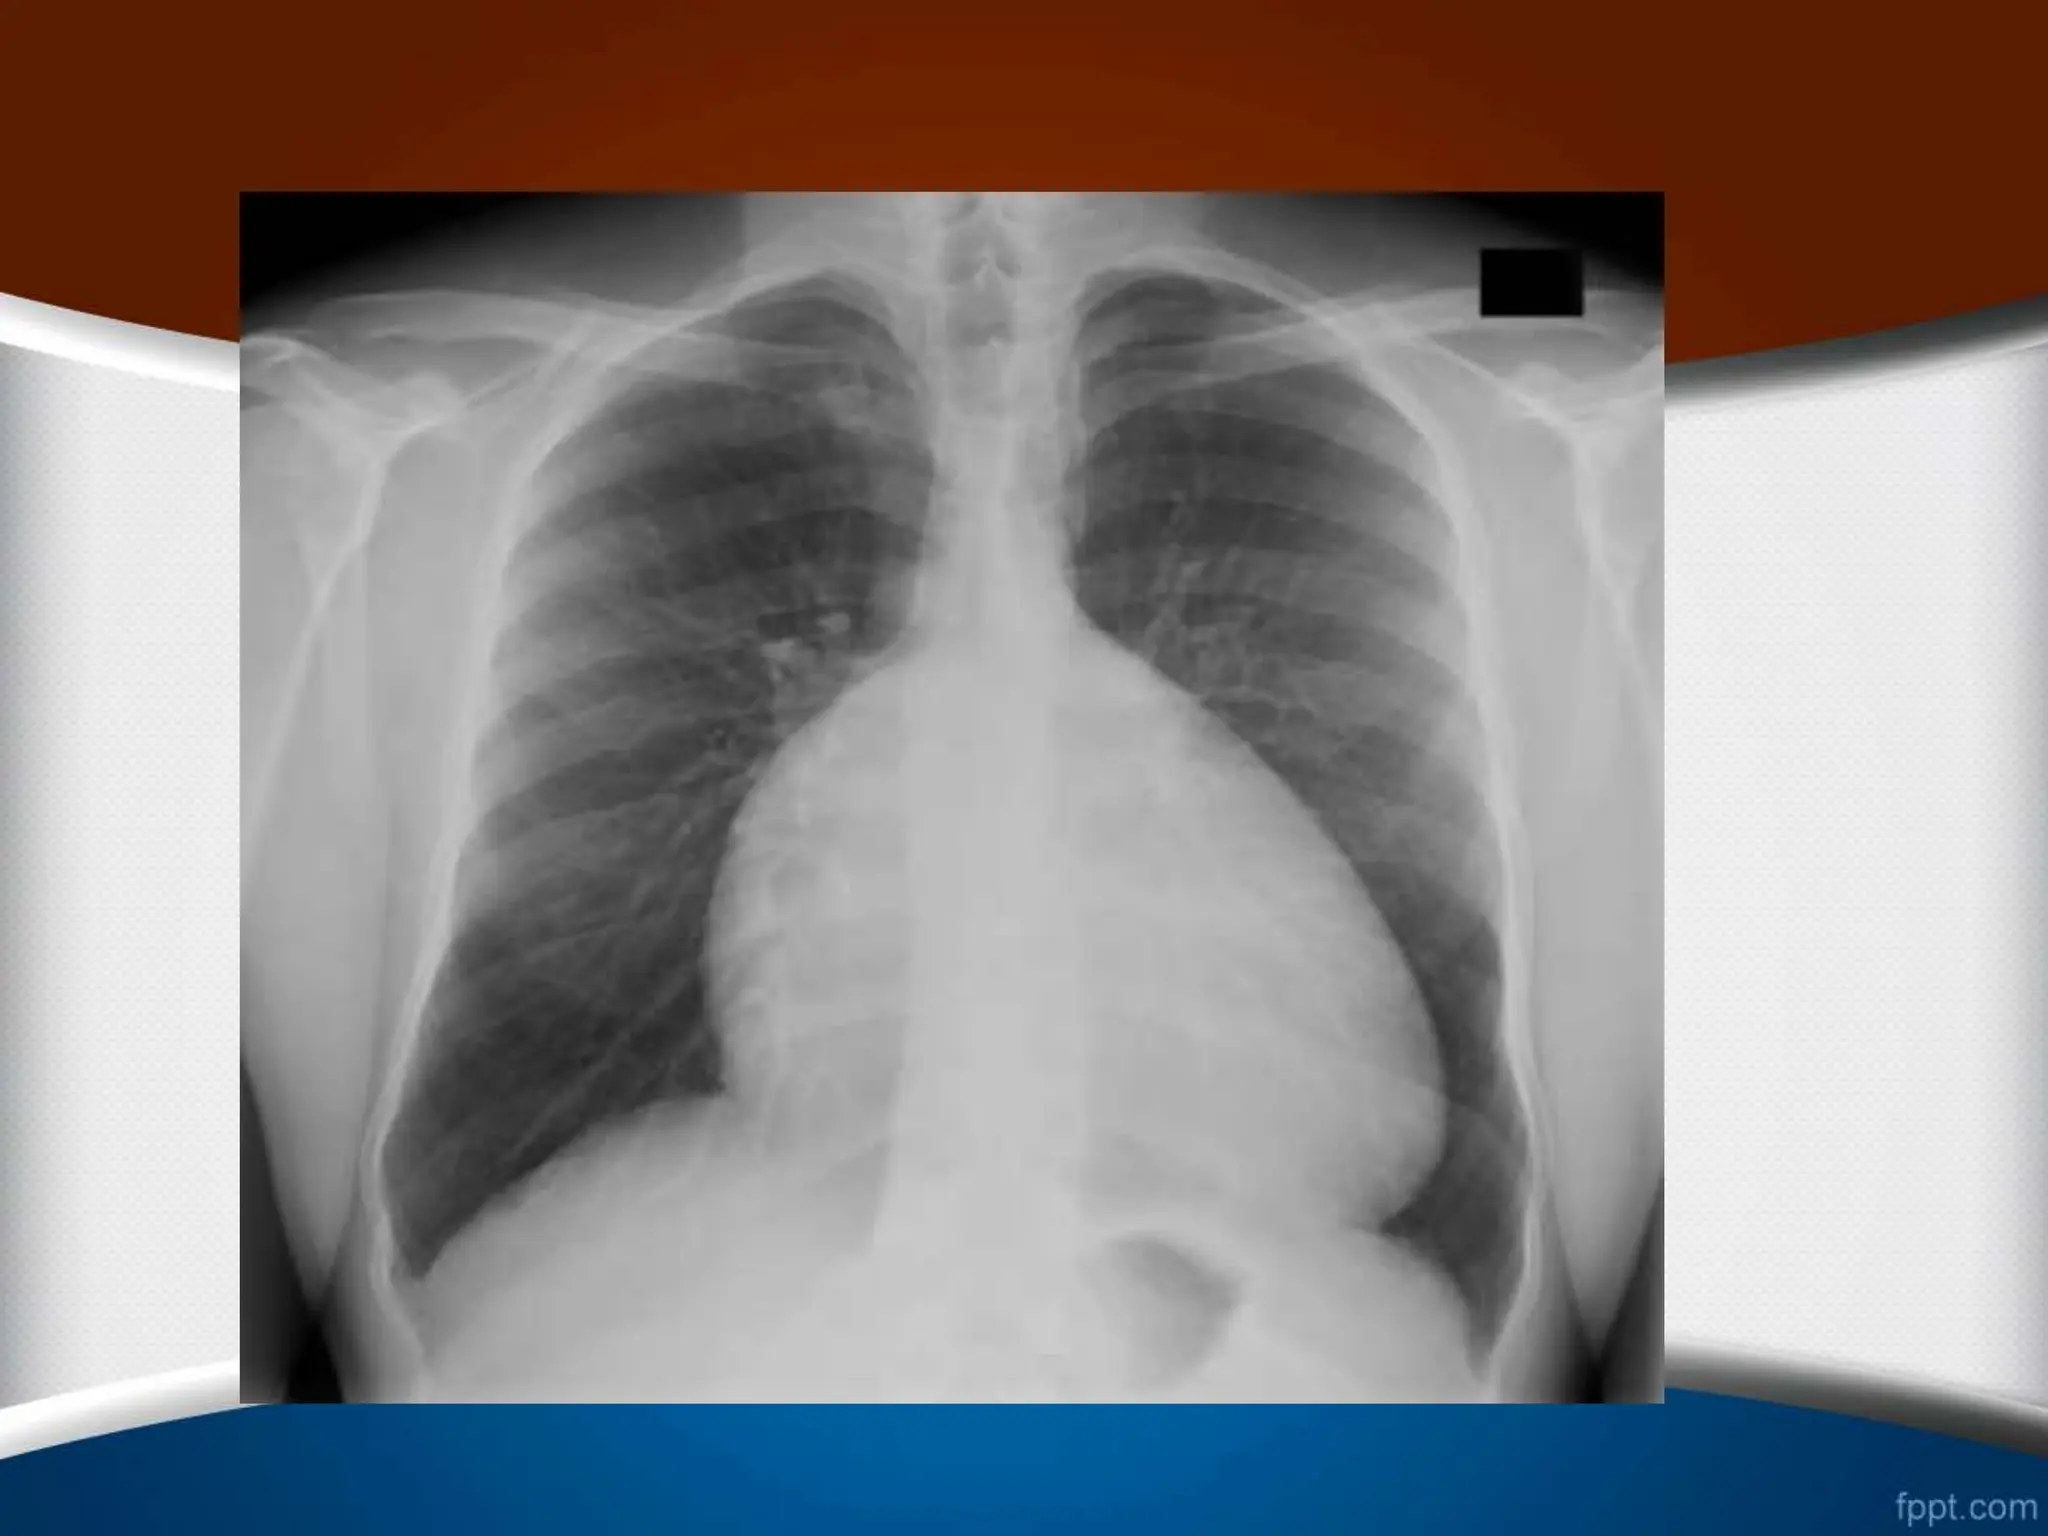

‫کاردیوتوراسیک‬ ‫نسبت‬ ‫نرمال‬ ‫حالت‬ ‫در‬

‫افراد‬ ‫در‬

‫از‬ ‫کمتر‬ ‫بالغ‬

50

%

‫است‬

‫این‬ ‫مسن‬ ‫افراد‬ ‫و‬ ‫کودکان‬ ‫در‬

‫نسبت‬

‫تا‬

55

‫باشد‬ ‫می‬ ‫قبول‬ ‫قابل‬ ‫هم‬

.

‫قلبی‬ ‫خارجی‬ ‫علل‬

‫یا‬ ‫پرتابل‬ ‫حالت‬ ‫در‬

AP

‫از‬ ‫فیلم‬ ‫حالت‬ ‫این‬ ‫در‬ ‫که‬ ‫شود‬ ‫گرفته‬

‫باعث‬ ‫و‬ ‫شود‬ ‫می‬ ‫نزدیک‬ ‫اشعه‬ ‫تیوب‬ ‫به‬ ‫بیمار‬ ‫و‬ ‫شده‬ ‫دور‬ ‫قلب‬

‫شود‬ ‫دیده‬ ‫تر‬ ‫بزرگ‬ ‫کاذب‬ ‫طور‬ ‫به‬ ‫قلب‬ ‫شود‬ ‫می‬

‫ب‬ ‫شود‬ ‫دیافراگم‬ ‫رفتن‬ ‫باال‬ ‫سبب‬ ‫که‬ ‫عاملی‬ ‫هر‬ ‫و‬ ‫آسیت‬ ،‫چاقی‬

‫اعث‬

‫شود‬ ‫می‬ ‫قلب‬ ‫کاذب‬ ‫بزرگی‬